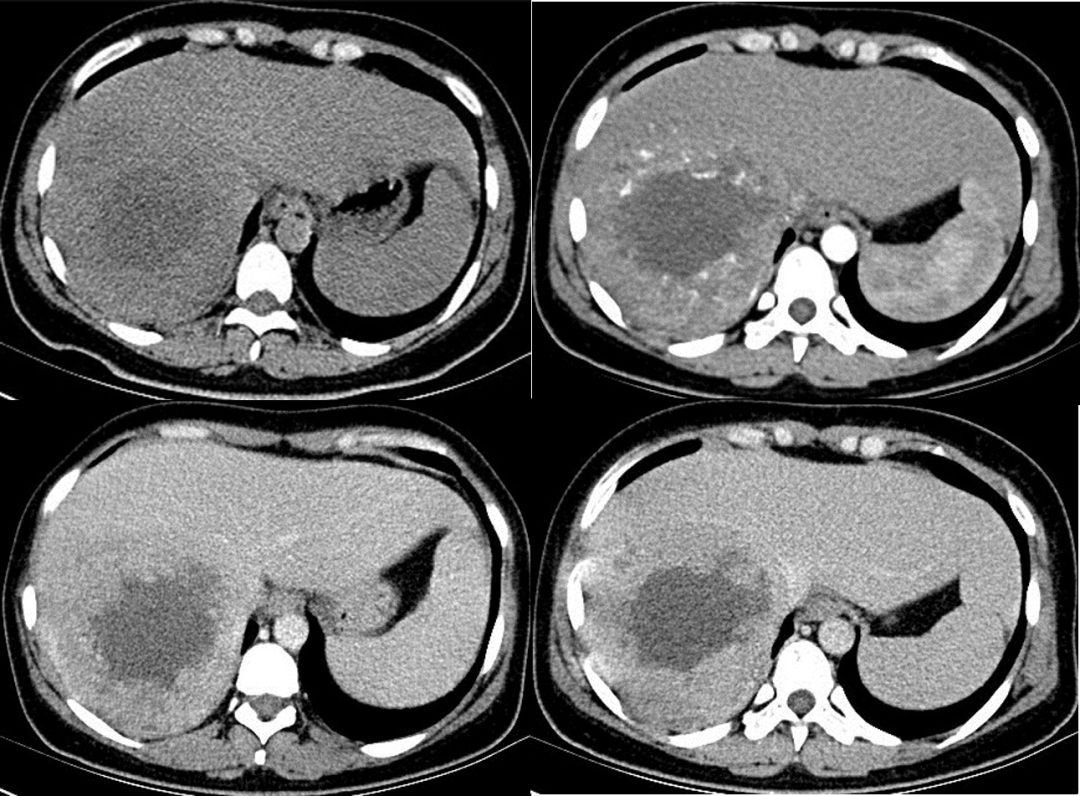

原发性肝细胞癌行三次debtace治疗一例

前入路右半肝切除术结合tace治疗巨大肝细胞癌——王学栋,清华大学